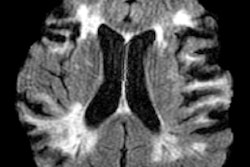

(Top) Absolute functional connectivity in a research subject for minutes five to 15 after he received the 57.75-mg intramuscular injection of ketamine. (Bottom) Subject's relative functional connectivity changes after the Ketamine took effect starting at minutes 15 to 25. Images courtesy of Kernel.For the pilot study, participants received either a low dose of ketamine and/or a placebo while wearing the Flow headset, which is equipped with sensors to record brain activity. Participants' experiences are being reported using structured questionnaires and validated assessments during study visits and at follow-up.